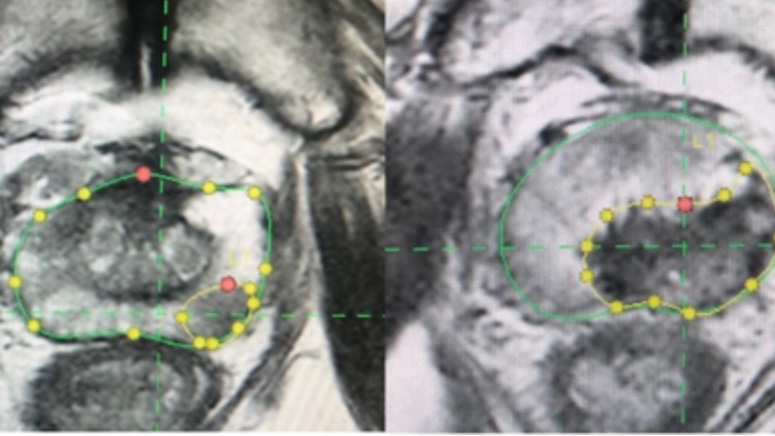

أجري العلاج تحت التخدير العام كإجراء ليوم واحد فقط. واعتمد التخطيط المسبق لمنطقة الاستئصال على صور الرنين المغناطيسي، مع إضافة هامش أمان لا يقل عن 5 ملليمتر حول الورم.

واستخدمت تقنيات توجيه مختلفة، شملت التوجيه الروبوتي في غالبية الحالات، أو دمج صور الأشعة المقطعية والرنين المغناطيسي مع الموجات فوق الصوتية.